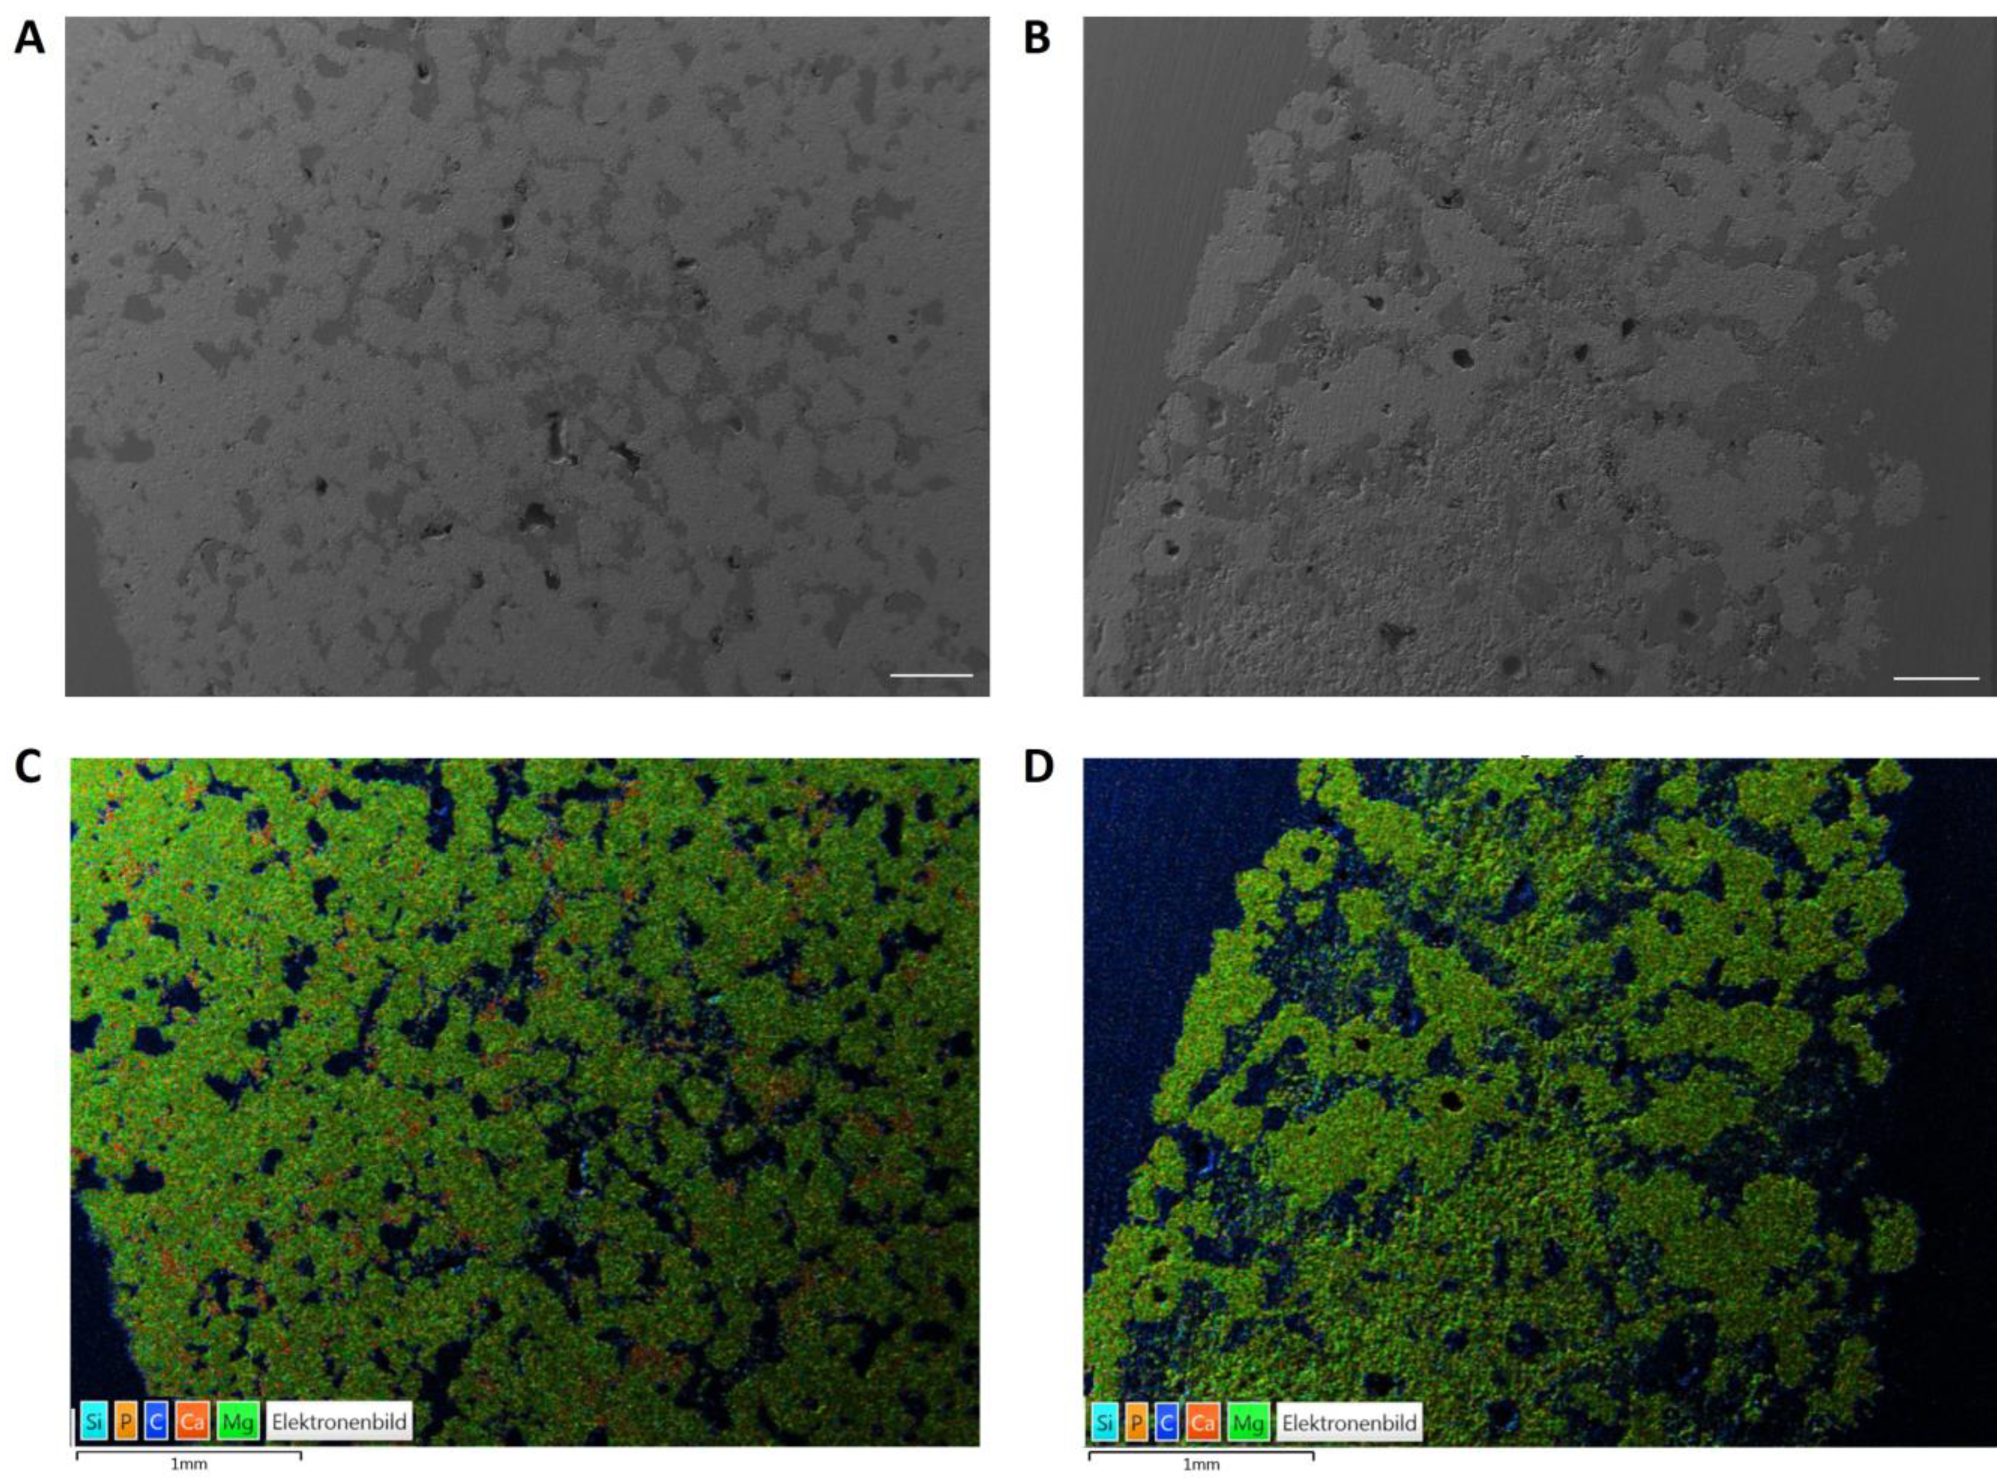

2.1.5. Energy Dispersive X-ray Analysis (EDX) and Scanning Electron Microscopy (SEM) before Implantation

3.2. SEM/EDX Analyses before Implantation

3.7. SEM/EDX Analyses after Implantation